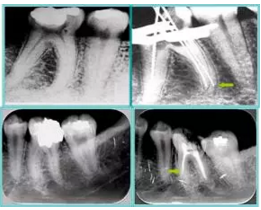

6. 術(shù)后 X 線片

術(shù)后 X 線片用來評定根管充填 長度、致密度(管壁清晰、側(cè)枝)等指標(biāo)。

圖為根管充填術(shù)后 X 線片。圖中可見,根管充填較好。右下圖有白色小點,為側(cè)方加壓導(dǎo)致糊劑擠出所致,表明根管充填比較致密。

致密、恰到好處的充填可去除干凈根管里感染灶,機(jī)體逐漸恢復(fù)。

多根牙時候需進(jìn)行偏移投照,正位投照無法說明具體哪根牙根管充填效果。